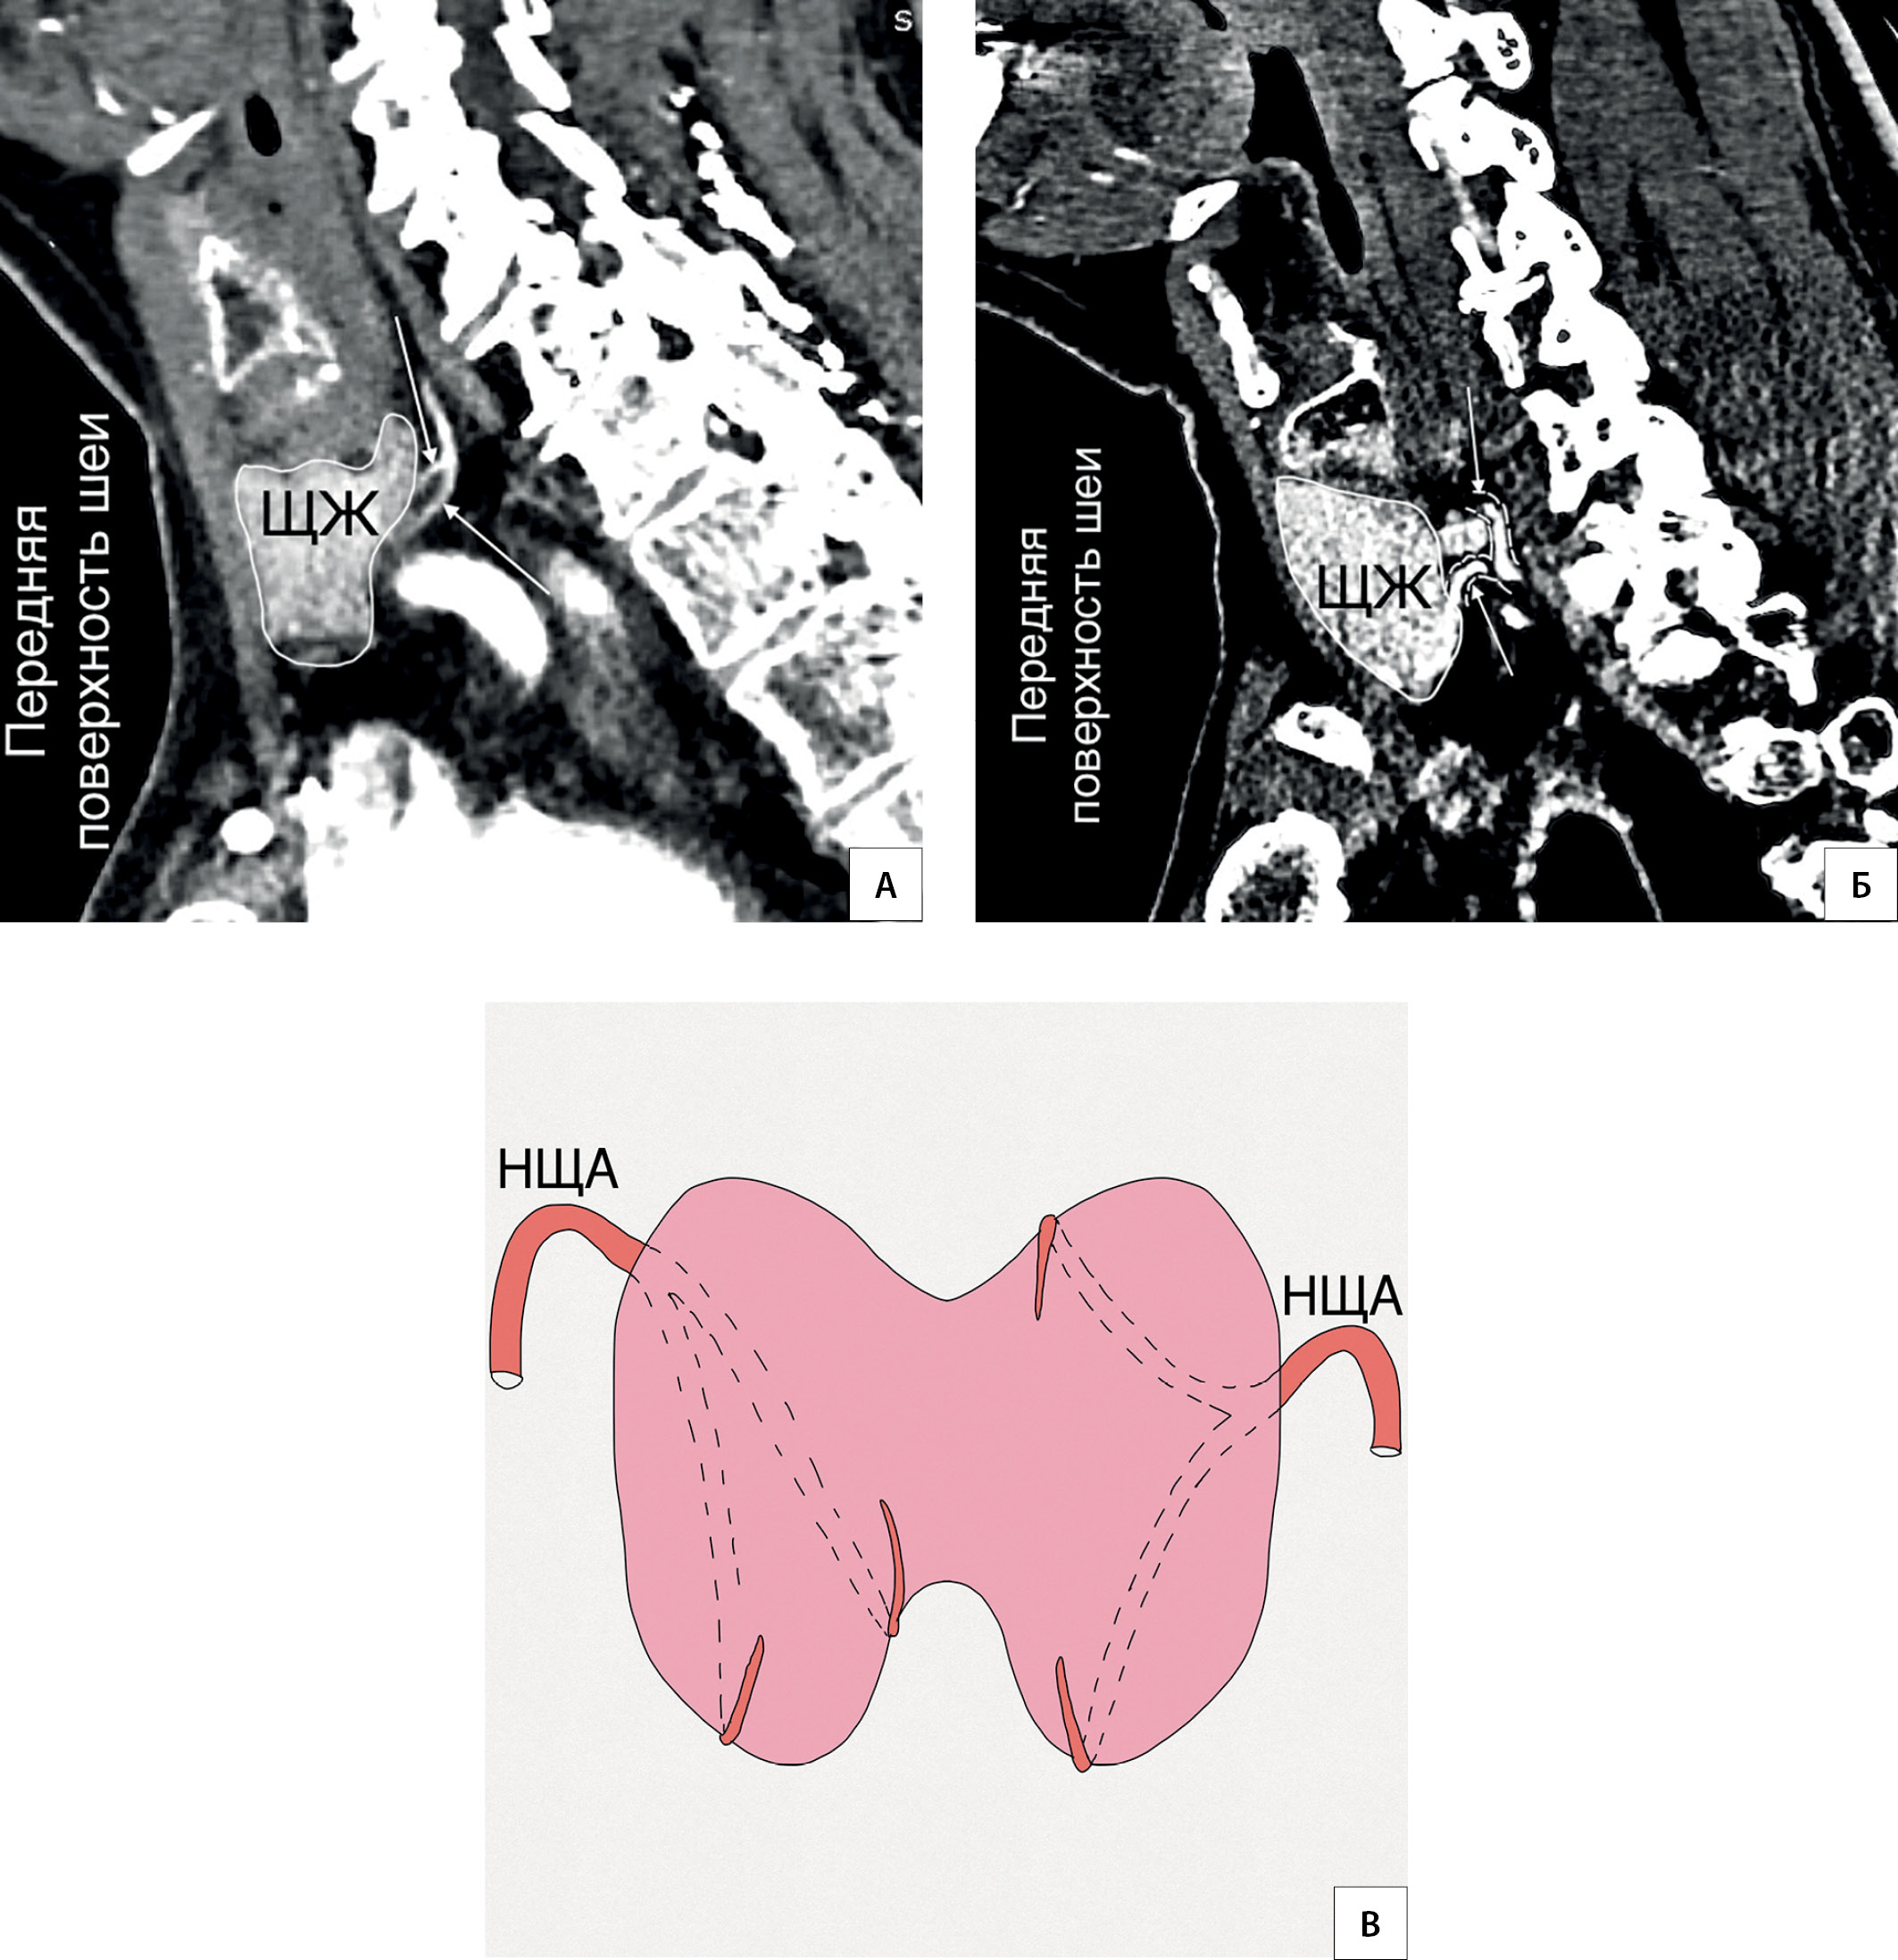

7. Рисунок 7. Нисходящая часть НЩА. А — КТ-ангиография (сагиттальный срез). Нисходящая ветвь НЩА направляется вниз вдоль задней поверхности доли ЩЖ; Б — КТ-ангиография (горизонтальный срез). Нисходящая часть НЩА располагается в пространстве между ЩЖ, пищеводом и длинной мышцей шеи. 2 — нисходящая часть НЩА; * — колено НЩА; MLC — musculus longus colli; E — esophagus; De — dextra; Si — sinistra.

8. Рисунок 8. Топография ветвей НЩА. А, Б, В, Г — КТ-ангиография (горизонтальный срез). Ветви НЩА располагаются по задней поверхности ЩЖ. Часть ветвей направляются в промежуток между долей ЩЖ и трахеей. C — a. carotis communis; V — a. vertebralis; S — a. subclavia; E — esophagus; De — dextra; Si — sinistra.

Тема

Тип Исследовательские инструменты

Посмотреть (608KB)

Метаданные ▾